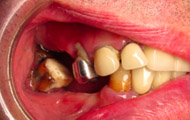

Exemple de 3 dents manquantes remplacées par 3 couronnes sur implants.

Pose des piliers prothétiques et des 3 couronnes scellées.

Exemple d’une réhabilitation complète implantaire

Situation clinique initiale

Situation clinique terminée